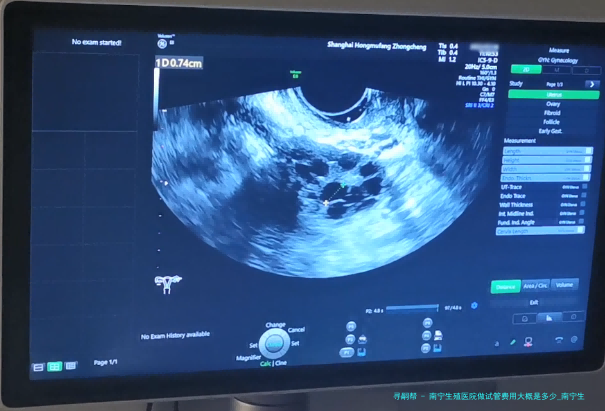

南宁生殖医院做试管费用大概是好多?试管婴儿已然成为许多不孕夫妻实现生育愿望的重要方法其中之一。南宁生殖医院作为专门从事辅助生殖医学的医疗机构,为不孕夫妇提供了精良的试管婴儿服务。如此南宁生殖医院做试管费用大概是几何呢?接下来将细致说明。